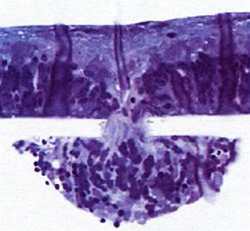

Разрез под микроскопом: клетки сетчатки крысы мигрируют через крошечное отверстие имплантата

Чтобы разрешить это противоречие, авторы нового проекта провели ряд опытов на крысах. И обнаружили новый биологический эффект. Ученые внедряли в сетчатки животных полимерные пластинки с маленькими отверстиями — диаметром 15–40 микрон. И вот через считанные часы клетки сетчатки сами начали передвигаться в отверстия, в течение всего нескольких дней заполняя полости под ними. Аналогично клетки вели себя и по отношению к пластине, которую покрывали стройные ряды длинных выступов-башенок. Клетки быстро заполняли промежутки между этими выступами.